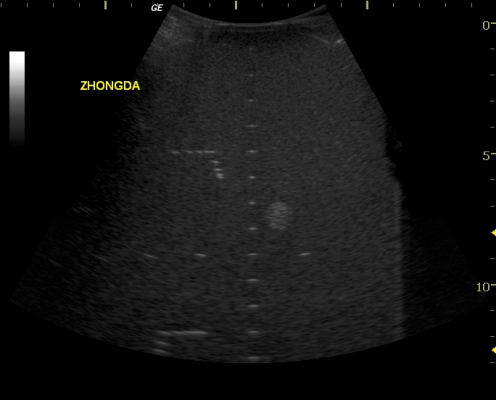

9,这是一个正常条件下,没做过什么调试的机器所打的模块图片,电子凸阵探头,频率4MHz,R=62,机子是一台用了一年多中档彩超,请问以各位专家的经验,10CM深处的图像可以接受吗,是否有问题?

凸阵探头监测图

9.这个可以接受。根据您的图像,调节一下参数的话120mm处横向分辨力不大于4mm,参考扇扫相控阵指标,符合规程要求。

[9]答:按照工程法,某个指标的检测结果能否被接受,要看标准如何规定,不是凭个人的目视感觉。10cm深处连分辨力靶群都没有,为何盯住这个地方,不明白。另外,凸阵的曲率半径系列为76,60,50,40,20,10,哪里出来个62?